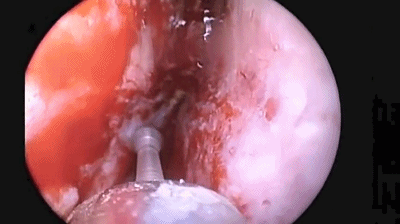

▼刮匙轻轻刮取肿瘤。

▼留取肿瘤标本。

▼本例垂体腺瘤质软,易于吸除。

▼继续仔细吸除瘤腔死角的肿瘤。